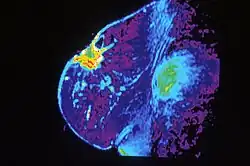

Mammography is the process of using low-energy X-rays (usually around 30 kVp) to examine the human breast, which is used as a diagnostic and screening tool. The goal of mammography is the early detection of breast cancer, typically through detection of characteristic masses and/or microcalcifications.

In addition to diagnostic purposes, mammography has interventional utility in stereotactic biopsies to precisely locate and find the area of concern and guide the biopsy needle to this precise location. This ensures that the area biopsies correlates to the abnormality seen on mammogram. It is called stereotactic since it uses images taken from two different angles of the same location. A biopsy is indicated when small accumulations of calcium are seen on mammogram, but cannot be felt on physical exam and do not appear on ultrasound.

Mammography overall has a false-positive rate of approximately 10%.[12] It has a false-negative (missed cancer) rate of between 7 and 12 percent.[13] This is partly due to dense tissues obscuring the cancer and the fact that the appearance of cancer on mammograms has a large overlap with the appearance of normal tissues. Additionally, mammogram should not be done with any increased frequency in people undergoing breast surgery, including breast enlargement, mastopexy, and breast reduction.[14]